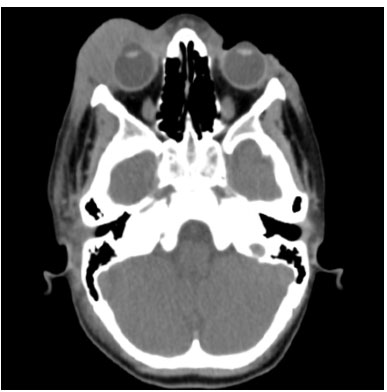

A tomografia computadorizada do crânio permite a avaliação detalhada das estruturas ósseas e das partes moles intracranianas. O conhecimento da anatomia em cortes axiais, coronais e sagitais é fundamental para a correta interpretação dos exames.

Figura 1: Cortes axiais de TC de crânio mostrando estruturas anatômicas principais